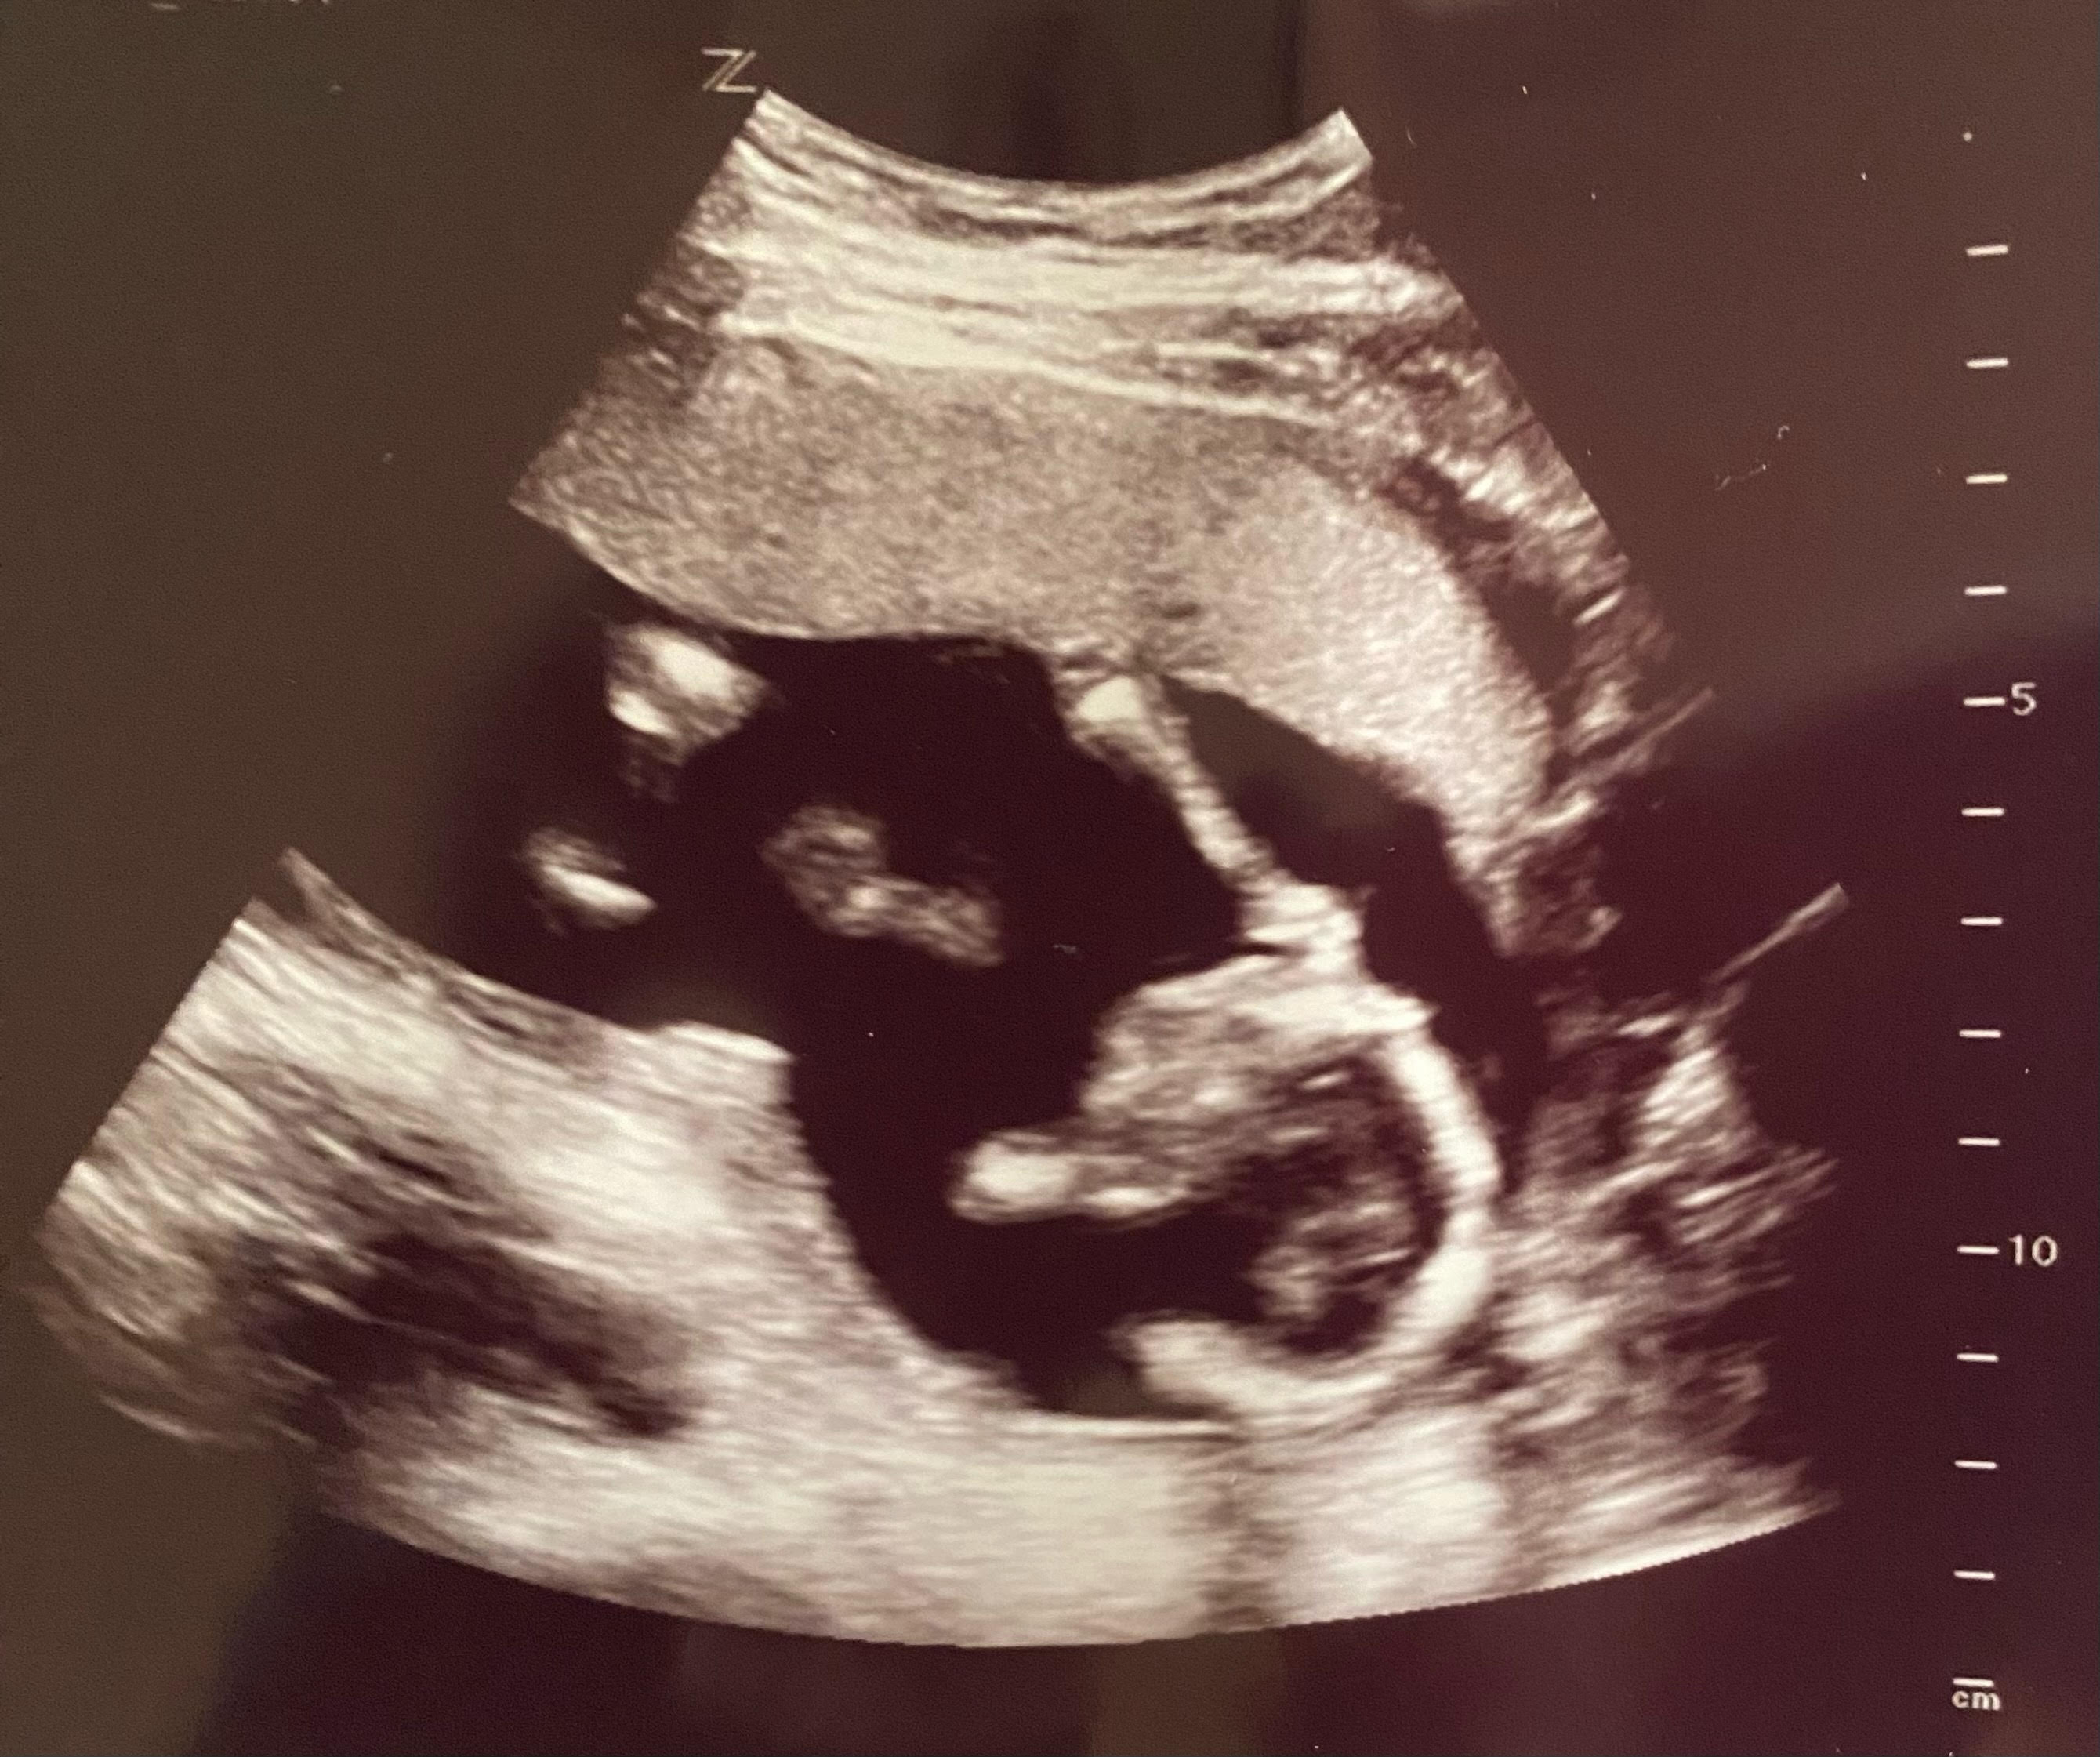

Hace un año, estábamos pasando por nuestra inseminación intrauterina, haciéndonos la prueba de embarazo y navegando por la vida como recién embarazados. Hace un año, en esta misma época, lo único que teníamos eran nuestra imaginación y nuestras conversaciones. Las mismas conversaciones que habíamos tenido durante años, pero esta vez sabiendo que nuestros sueños finalmente se harían realidad. Ese día en el baño fue la primera vez que nuestra familia estuvo junta. Pasamos los siguientes meses leyendo qué fruta era nuestro bebé semana tras semana, viéndolo crecer en cada ecografía y sintiendo sus primeras vueltas, hipos y patadas a medida que pasaban los trimestres. Nunca nos cansábamos de ello. Cada movimiento era una confirmación de que nuestra familia estaba creciendo oficialmente.